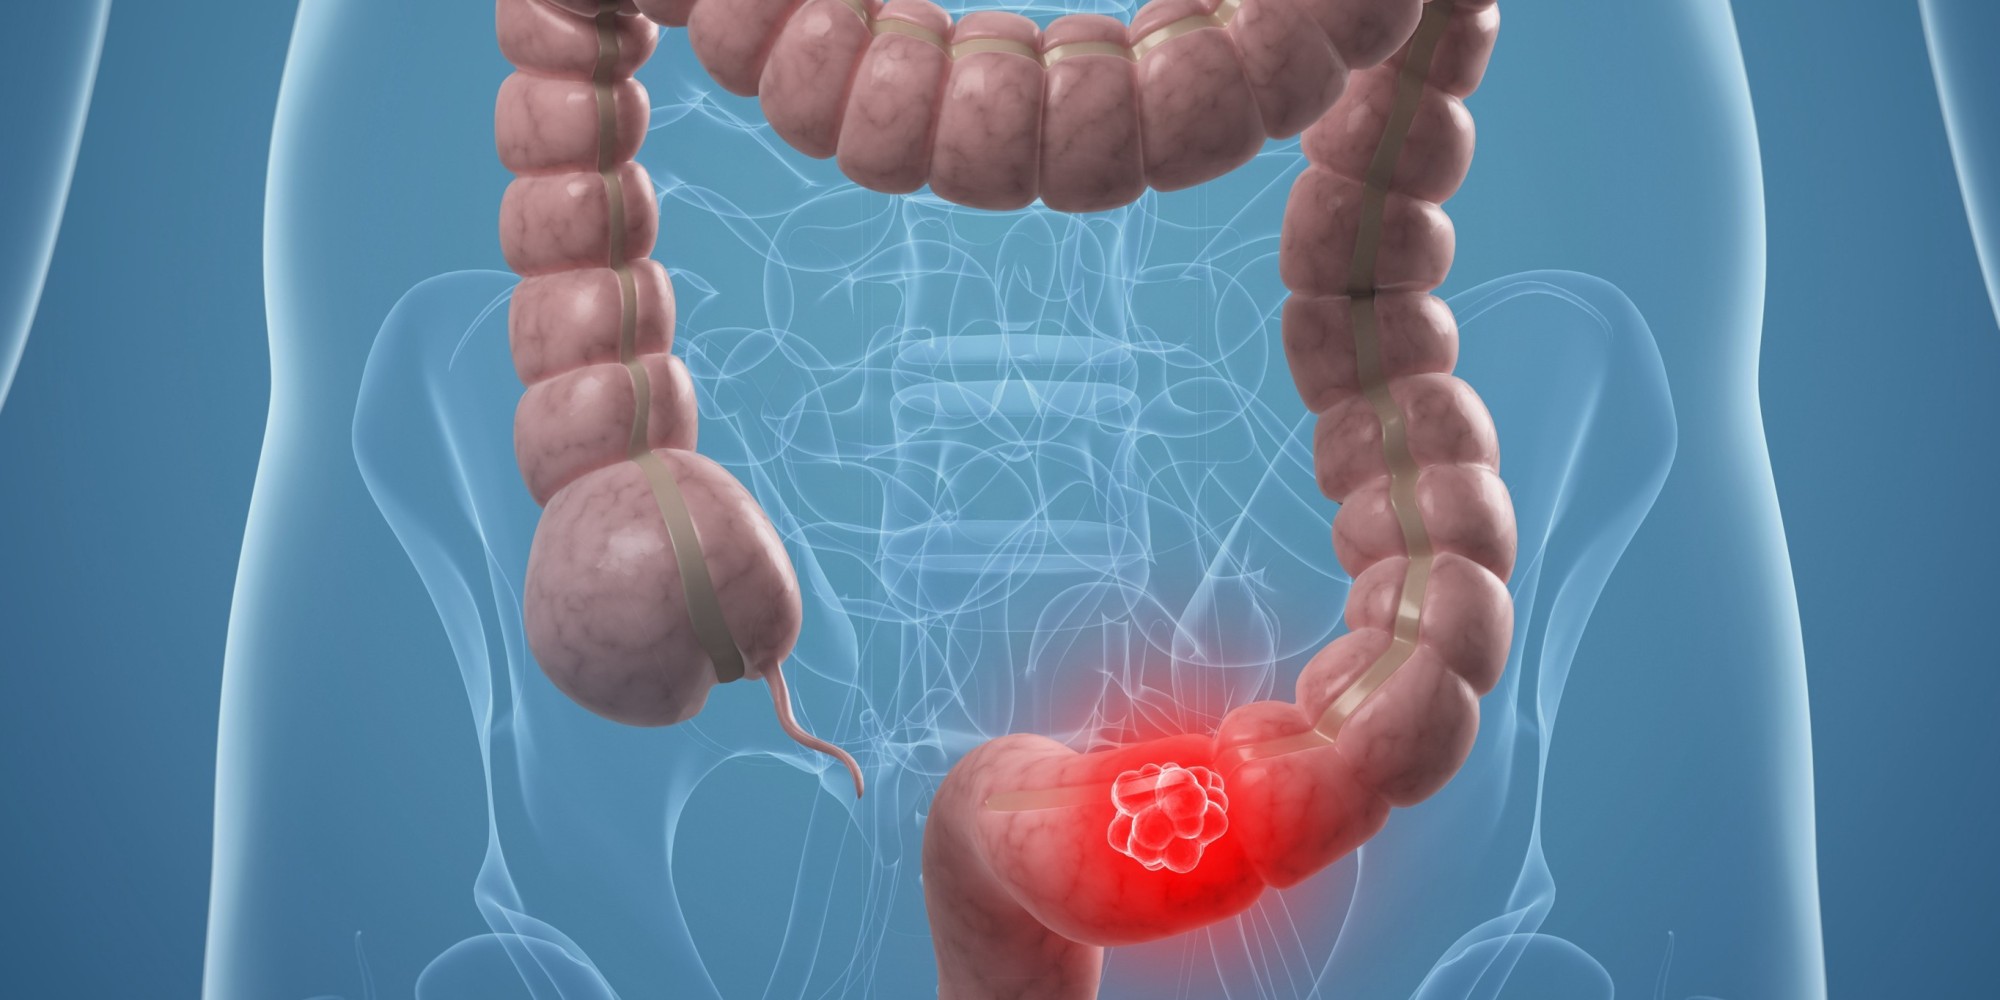

Ο καρκίνος του παχέος εντέρου ανήκει στις πιο κοινές μορφές καρκίνου.

Στα εσωτερικά τοιχώματα του εντέρου αναπτύσσονται πολύποδες, οι οποίοι μπορεί να εξελιχθούν σε καρκίνο αν τα κύτταρα αρχίσουν να πολλαπλασιάζονται ανεξέλεγκτα.